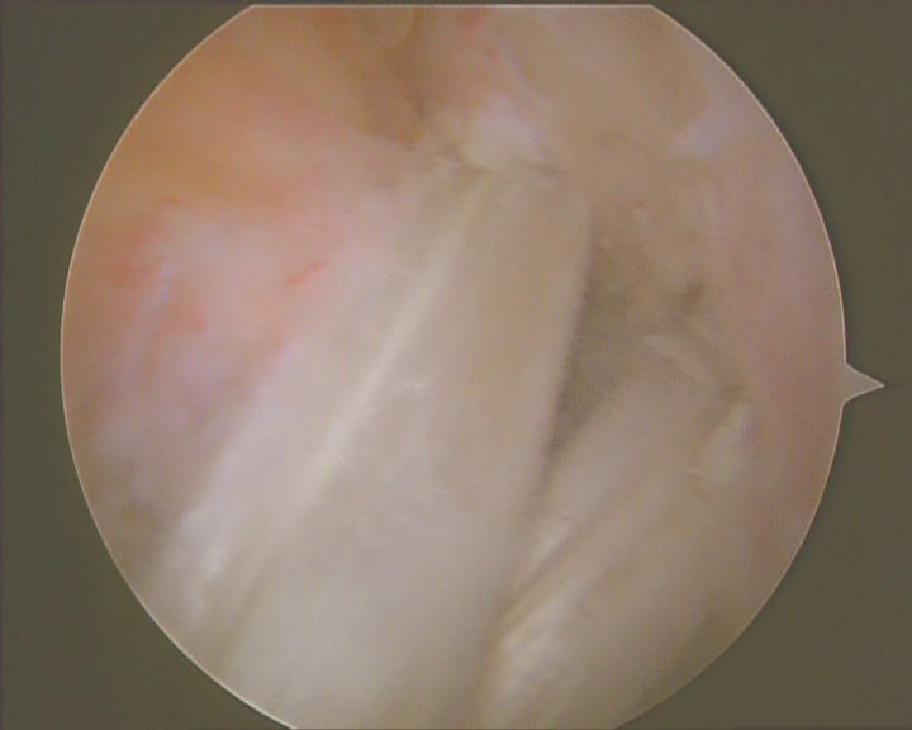

关节镜下观

正常前交叉韧带

前交叉韧带损伤后形成的疤痕组织